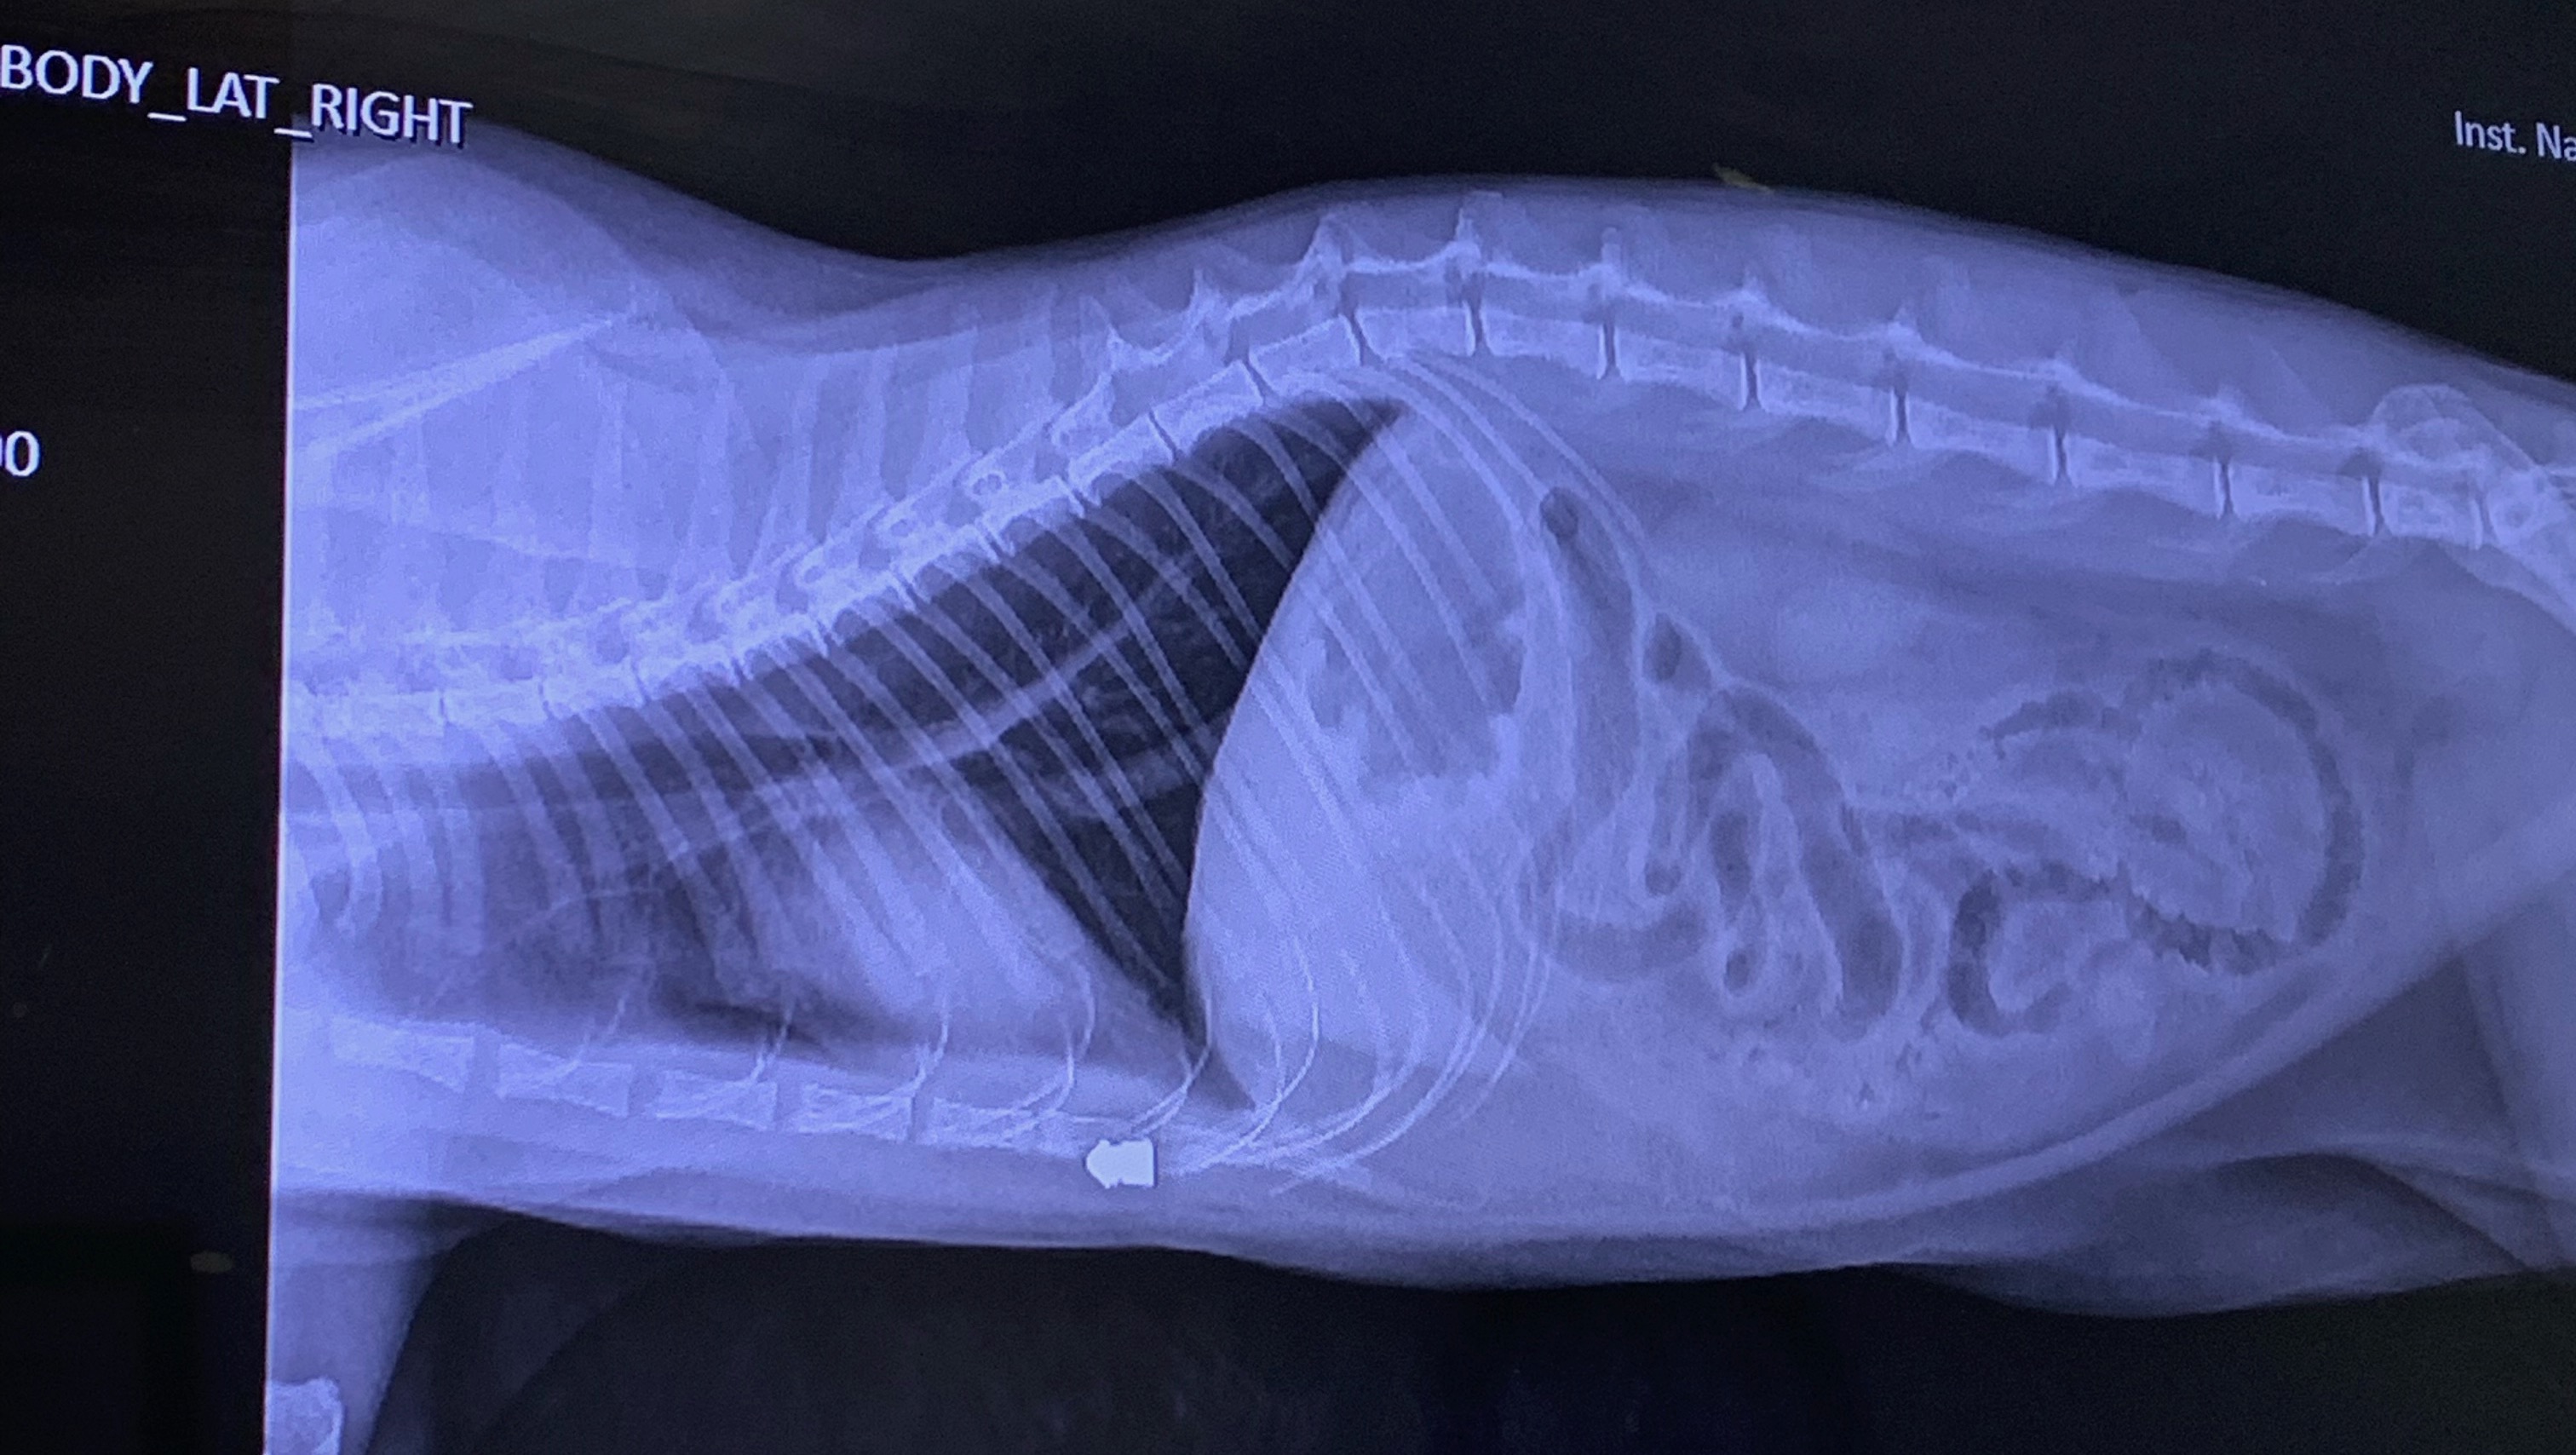

Hi, my name is Mariah. As many of you may have heard, my cat was shot with a pellet gun at our complex, Seabreeze Townhomes, off harbor and Wilson. The bullet, unfortunately, went through his body hitting his spine and lodged itself below the abdomen. Rexy had to get emergency surgery and almost died. We’re not sure if it’s just him healing, but he still can’t use his back right leg very well and we’re worried it’s because the bullet hit the spine. Regardless, he is on the mend and feeling much better, but our vet bill for everything was $3500. Please donate if you are able. Anything is appreciated. Thank you